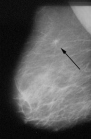

Archibald Leman Cochrane, Portrait [22], an analyst and logician of medicine.

Critic doctor Archibald Cochrane (1909-1988) founds the medicine statistics

(p.71-73)

-- with the thesis that the early detection of breast cancer harms more than it's useful

-- he founded the Archie-Cochrane-Center in Copenhague with a Cochrane library

-- there is always the principle that nothing is "holy"

-- and there is always the principle: "What is sounding logic does not have to be logic" (p.71).

X-ray equipment in the camp of Hilburghausen

With the X-ray equipment can be performed a really precise investigation about virulence or outbreak of TB in the camp (p.76-77). But there is also the moment when the German surgeon major rejects any further medical investigation for the affected telling to Cochrane: "Doctors are super fluent!" (p.78)

[All in all the X-ray equipment is not a big progress against the illness[.

Since 1943 Cochrane is performing precise statistics about the ill inmates and with this his first own epidemiological work is beginning (p.77).

In 1945 Cochrane is finishing his camp statistics:

Cochrane's table about tuberculosis lethal cases in war prisoner's camps 1941-1945, psychological factor of food care parcels

Inmates

Remark

Death rate

Russians

without food care parcels

5.1% got TB

Frenchmen

with arbitrary partially higher food rations

0.2% got TB

British

with food care parcels

0 TB

(p.77)